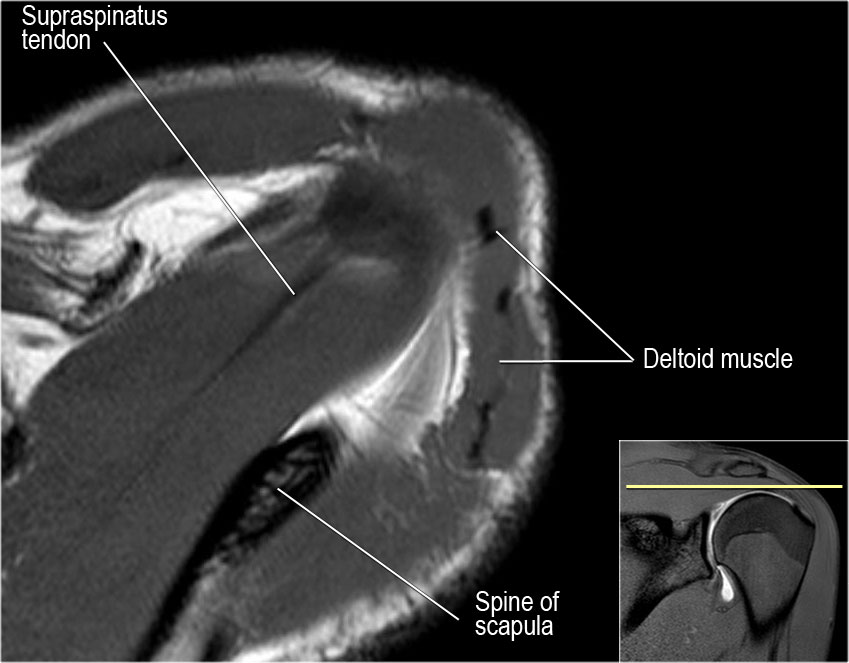

Axial anatomy and checklist

- Look for an os acromiale.

- Notice that the supraspinatus tendon is parallel to the axis of the muscle. This is not always the case.